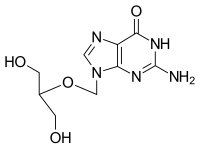

IUPAC name

| Formula | C9H13N5O4 |

| Molar mass | 255.234 g·mol−1 |

SMILES

InChI